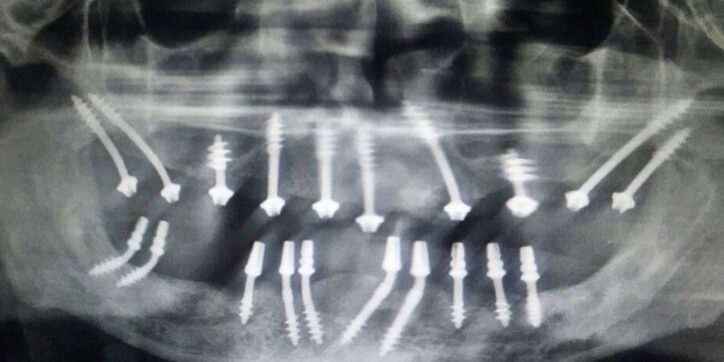

The basal implantology, which is also called cortical, or biocortical implant system, has been developed and it includes the positioning of implants at the basal cortical bone, which offers exceptional quality cortical bones because of preservation of those complex implants. The basal implant would be the most innovative among implants, effective for any state of bone. It may be used on patients who have any bone density and any bone mass. These implants participate in the exceptionally dense cortical bone that has the least propensity to get resorption. Basal-bone is found in everybody, despite acute bone loss due to gum disease or lack of teeth.

The basal implant is also known as orthopedic implants since they apply principles of esophageal surgery unlike the normal dental implants available. They’re also called lateral or disk implants. A significant reason to utilize the bone to put the implants rather than the alveolar bone is that the stress-bearing field of dental implant placement website at the alveolar bone may also be filled with teeth instantly.

There are two forms of basal implants, namely BOI and basal cortical screw (BCS) implants. The BCS was created up to 12 millimeter diameter and may be inserted directly into the extraction socket.

BOI implants are primarily utilized in several instances as long edentulous length or in conditions where multiple teeth need to be extracted or as soon as the traditional 2-stage implant positioning or bone augmentation has neglected. It’s also utilized in the event of rather thin ridges because of the decreased buccolingual depth of the bone or in patients with inadequate bone elevation.

Lateral basal implants are the kind of implants that are placed in the lateral facet of the jawbone and are restricted to the bone structures, and also the load transmission is mostly moved to the horizontal augmentation sections.